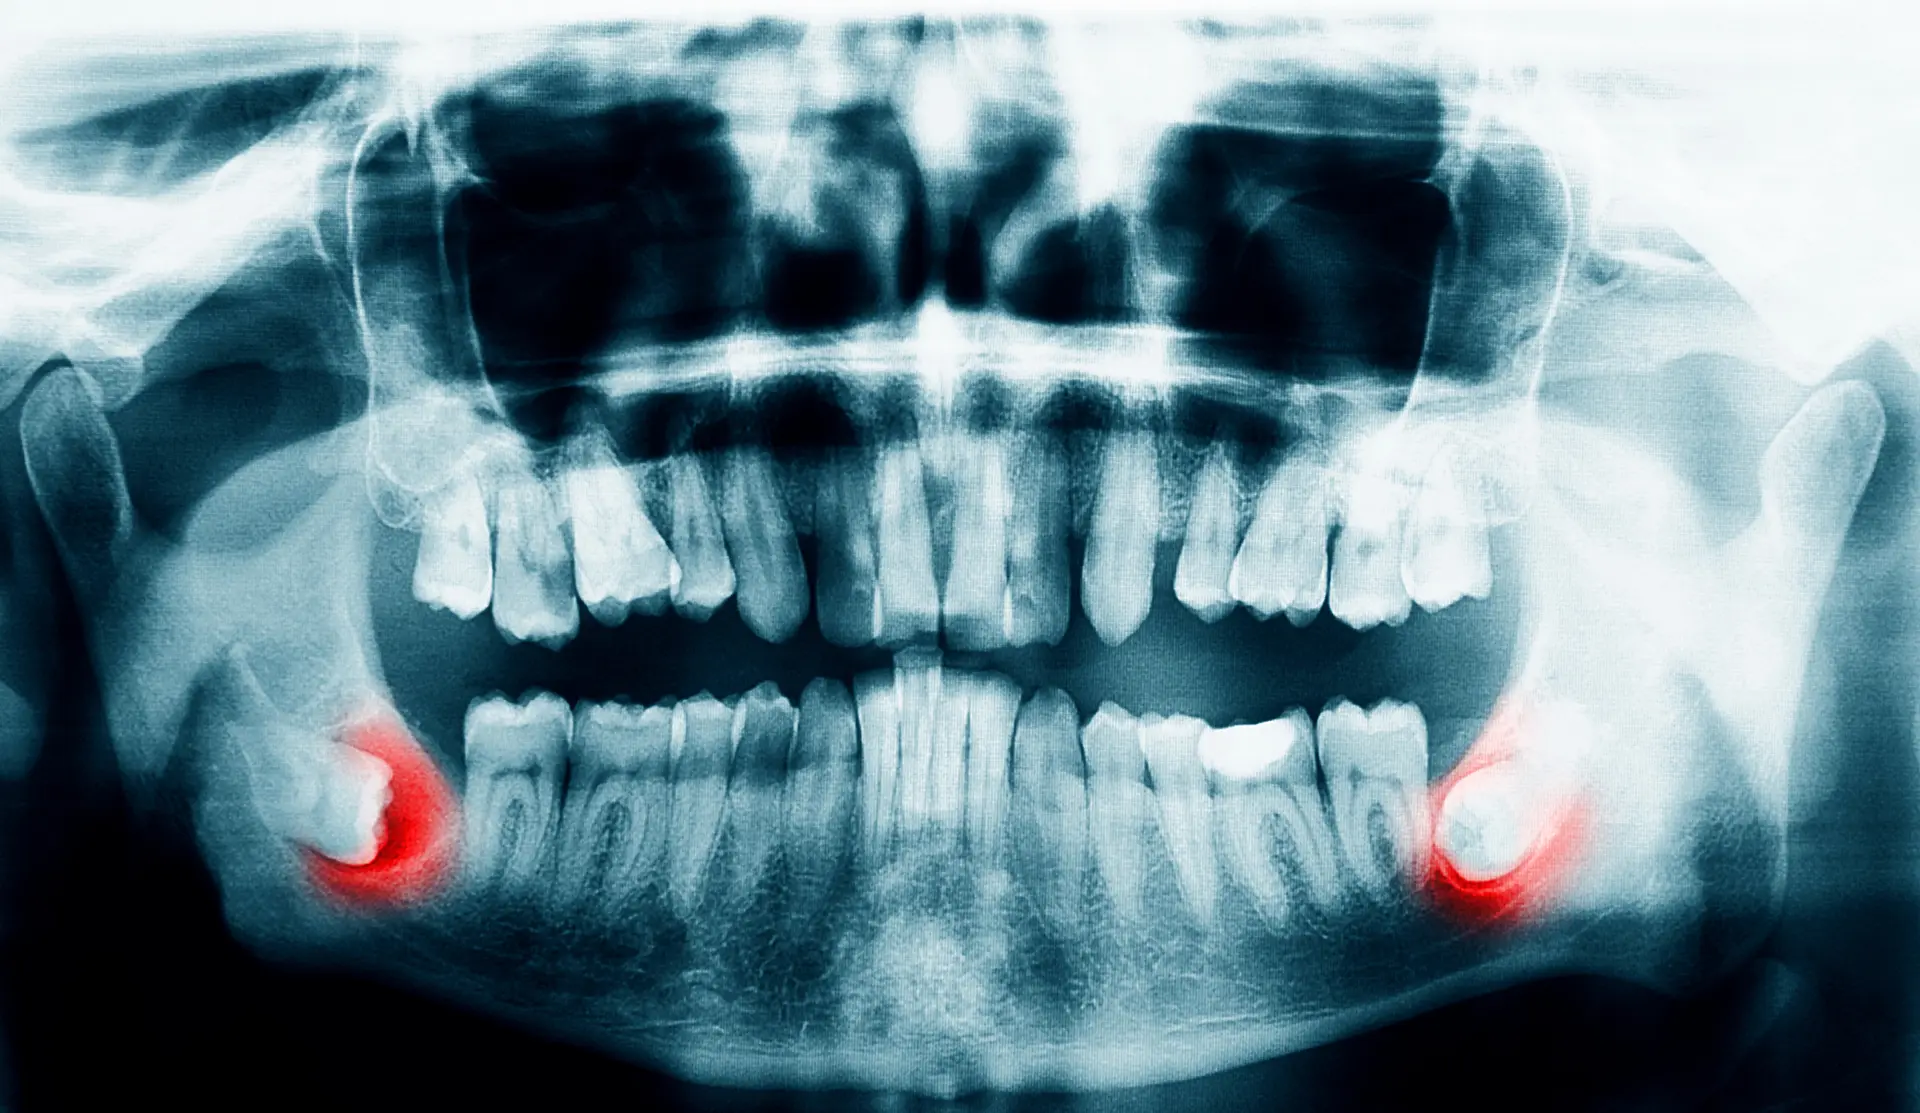

Wisdom teeth often have to be extracted to ensure the rest of your teeth stay healthy. Most wisdom teeth erupt misaligned, which can cause tooth crowding and disruption in your teeth and gums. This is not only painful but can make oral hygiene more difficult. Another common reason for wisdom teeth extraction is a partial eruption. This encourages bacteria to accumulate in the pockets of your gums, putting you at risk for gum disease, infection, and tooth decay. That being said, sometimes wisdom teeth don’t always need to be removed. If your wisdom teeth erupt properly aligned and don’t impact your other teeth, your doctor may not recommend extraction. But generally, wisdom teeth need to be removed to preserve a healthy smile.